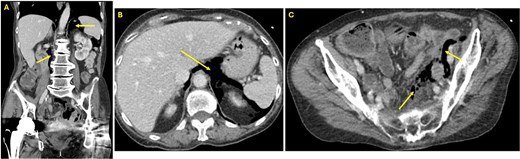

At presentation to the Emergency Department, she reported painless rectal bleeding. On physical exam, her abdomen was nontender, with mild distension and minimal bleeding was noted at the anus. Laboratory findings demonstrated leukocytosis (WBC 13.4 × 103/μl) and mild anemia (Hb 10.8 g/dl). Computed tomography (CT) of the abdomen and pelvis revealed extraluminal gas near the rectal anastomosis, with gas tracking along the mesocolon into the retroperitoneum and mediastinum (Fig. 1A–C), findings consistent with iatrogenic perforation.

(A) Coronal view CT of the abdomen and pelvis showing free air in the retroperitoneum (arrows). (B) Axial view CT of the abdomen and pelvis at the level of the liver demonstrating free air in the retroperitoneum (arrow). (C) Axial view CT in the pelvis revealing free air in the colonic mesentery (arrows), consistent with extraluminal gas from rectal perforation.